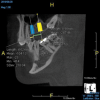

(8.) An original finding of a small lesion on the mesial root of tooth No. 30 was not accompanied by any outward symptoms; therefore, the patient delayed pursuing treatment. When a follow-up CBCT scan was acquired 6 years later, the easy-to-visualize increase in the dimensions of the lesion motivated the patient to elect a treatment plan.

Figure 8

(9.) An original finding of a small lesion on the mesial root of tooth No. 30 was not accompanied by any outward symptoms; therefore, the patient delayed pursuing treatment. When a follow-up CBCT scan was acquired 6 years later, the easy-to-visualize increase in the dimensions of the lesion motivated the patient to elect a treatment plan.

Figure 9

Identifying the shape and location of the roots of teeth to be removed is critical to performing safe exodontia. Some clinicians virtually deconstruct teeth using CBCT images prior to actually sectioning and removing them. Being able to recognize pathoses and differentiate affected structures from normal structures is key in deciding what the treatment should be and when that treatment should be initiated (Figure 8 through Figure 10). The arena of the oral surgeon is larger than that of many general practitioners, involving the sinuses and condyles and other considerations in and around the entire mandible and maxilla. Certain fractures and other conditions that some general practitioners feel uncomfortable treating are often referred for evaluation and treatment by an oral surgeon. Because of this, oral surgeons require the most accurate and complete diagnostic information available. The American Academy of Oral and Maxillofacial Radiology recommends that "cross-sectional imaging be used for the assessment of all dental implant sites" and has stated that "CBCT is the imaging method of choice for gaining this information."18